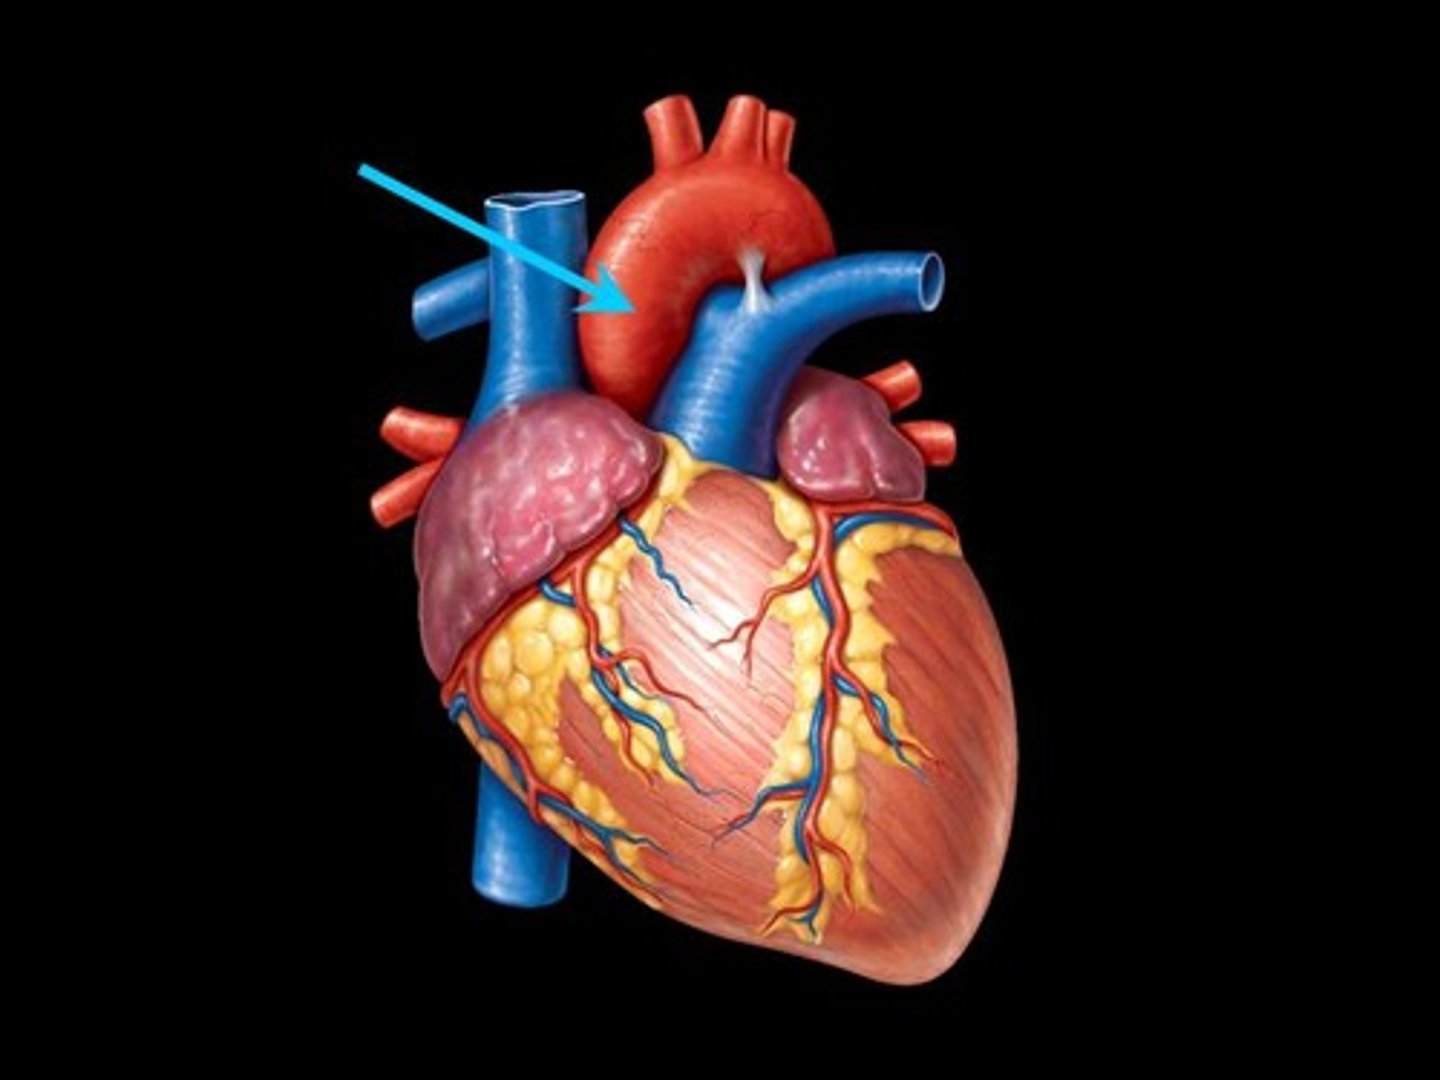

superior vena cava